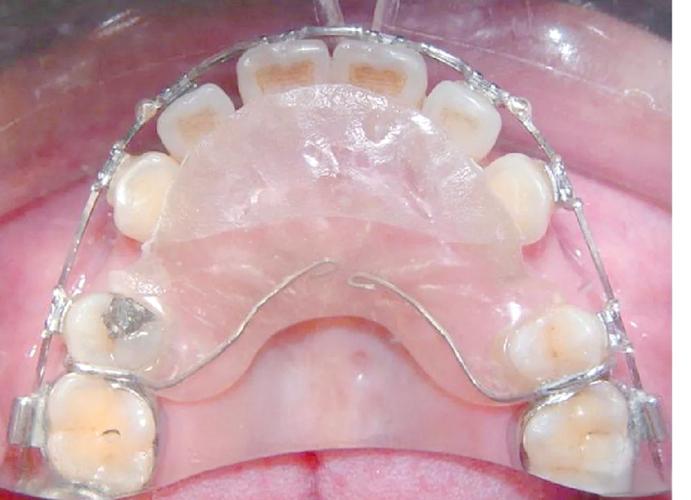

Hawley保持器

由树脂基托和钢丝卡环组成,钢丝可弯制调整,适用于多数病例,基托可增加舒适度。

透明压膜保持器

通过热压膜技术将聚乙烯醇材料压制成与牙齿贴合的薄膜,完全包裹牙齿,美观度高,适用于无拔牙的简单病例。

固定保持器

粘接于牙齿舌侧的细钢丝, bonded于前牙区,用于防止前牙复发,尤其适用于下牙列。